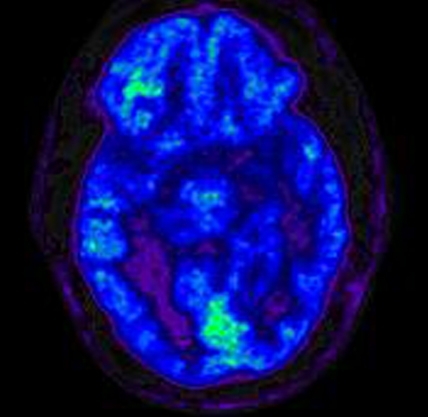

Positron Emission Topography (PET)

Positron Emission Tomography Scan (PET) measures brain metabolism. Different applications of PET allow one to "see" pathology associated with Alzheimer's disease, for instance, that cannot be visualized any other way. Used in a different way, PET also allows doctors to see how different areas of the brain use oxygen or glucose—both very important in understanding not just what the damage might look like but also how the brain provides energy to itself. In brain injury research, PET scans are used to identify how metabolic processes may be changed after a brain injury. For instance, the brain may absorb less glucose (sugar) after a brain injury, which may affect how an individual processes information. PET has recently been used in tandem with MRI to identify (with a high degree of spatial accuracy) specific brain regions that may be experiencing metabolic changes after injury.

“PET scans look at metabolism in the brain. We inject the radiotracer glucose, and the glucose is utilized in the brain, and areas of the brain that use more glucose light up stronger, and areas that use less glucose do not light up as strong. So, we can see areas of the brain that are potentially damaged and not utilizing glucose as much as they should be.” — Gerard Riedy, MD, PhD, neuroradiologist, National Intrepid Center of Excellence (NICoE), Walter Redd National Military Medical Center Bethesda